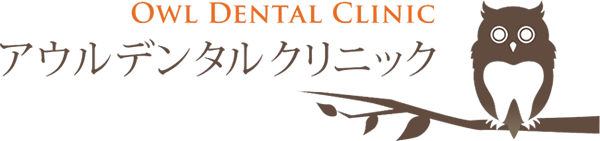

術前

金属の周りが黒くなっていたり、金属と歯の間に段差がある。

メタル除去後

虫歯により、黒く変色していたり、汚染された象牙質を認める。

セット後

自然な色合いと段差のないセラミック修復をすることができた。